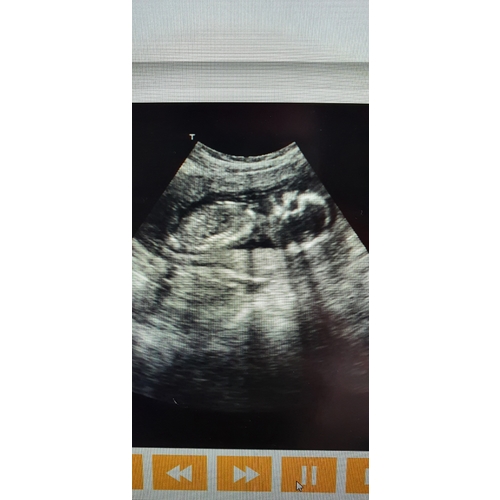

Hi ik heb de baby watcher 3 dagen gehad. Je moet niet het beste kwaliteit verwachten. Je kan niet alles duidelijk er mee zien je kan zien dat je kleine lekker beweegt en met geluk kan je het hartje zien. Bij mij was er gedoe bij het leveren op de dag zelf kregen we te horen dat die niet kwam en toen ik hem wou annuleren kon de baby watcher ineens op de post.

Mijn ervaring is als je zelf een goeie laptop hebt neem daar het pakket op zodat wellicht je beeld veel beter is je krijg hier best oudere laptops bij en de beeld kwaliteit is gewoon niet het beste. Als ik het had geweten had ik me eigen laptop genomen